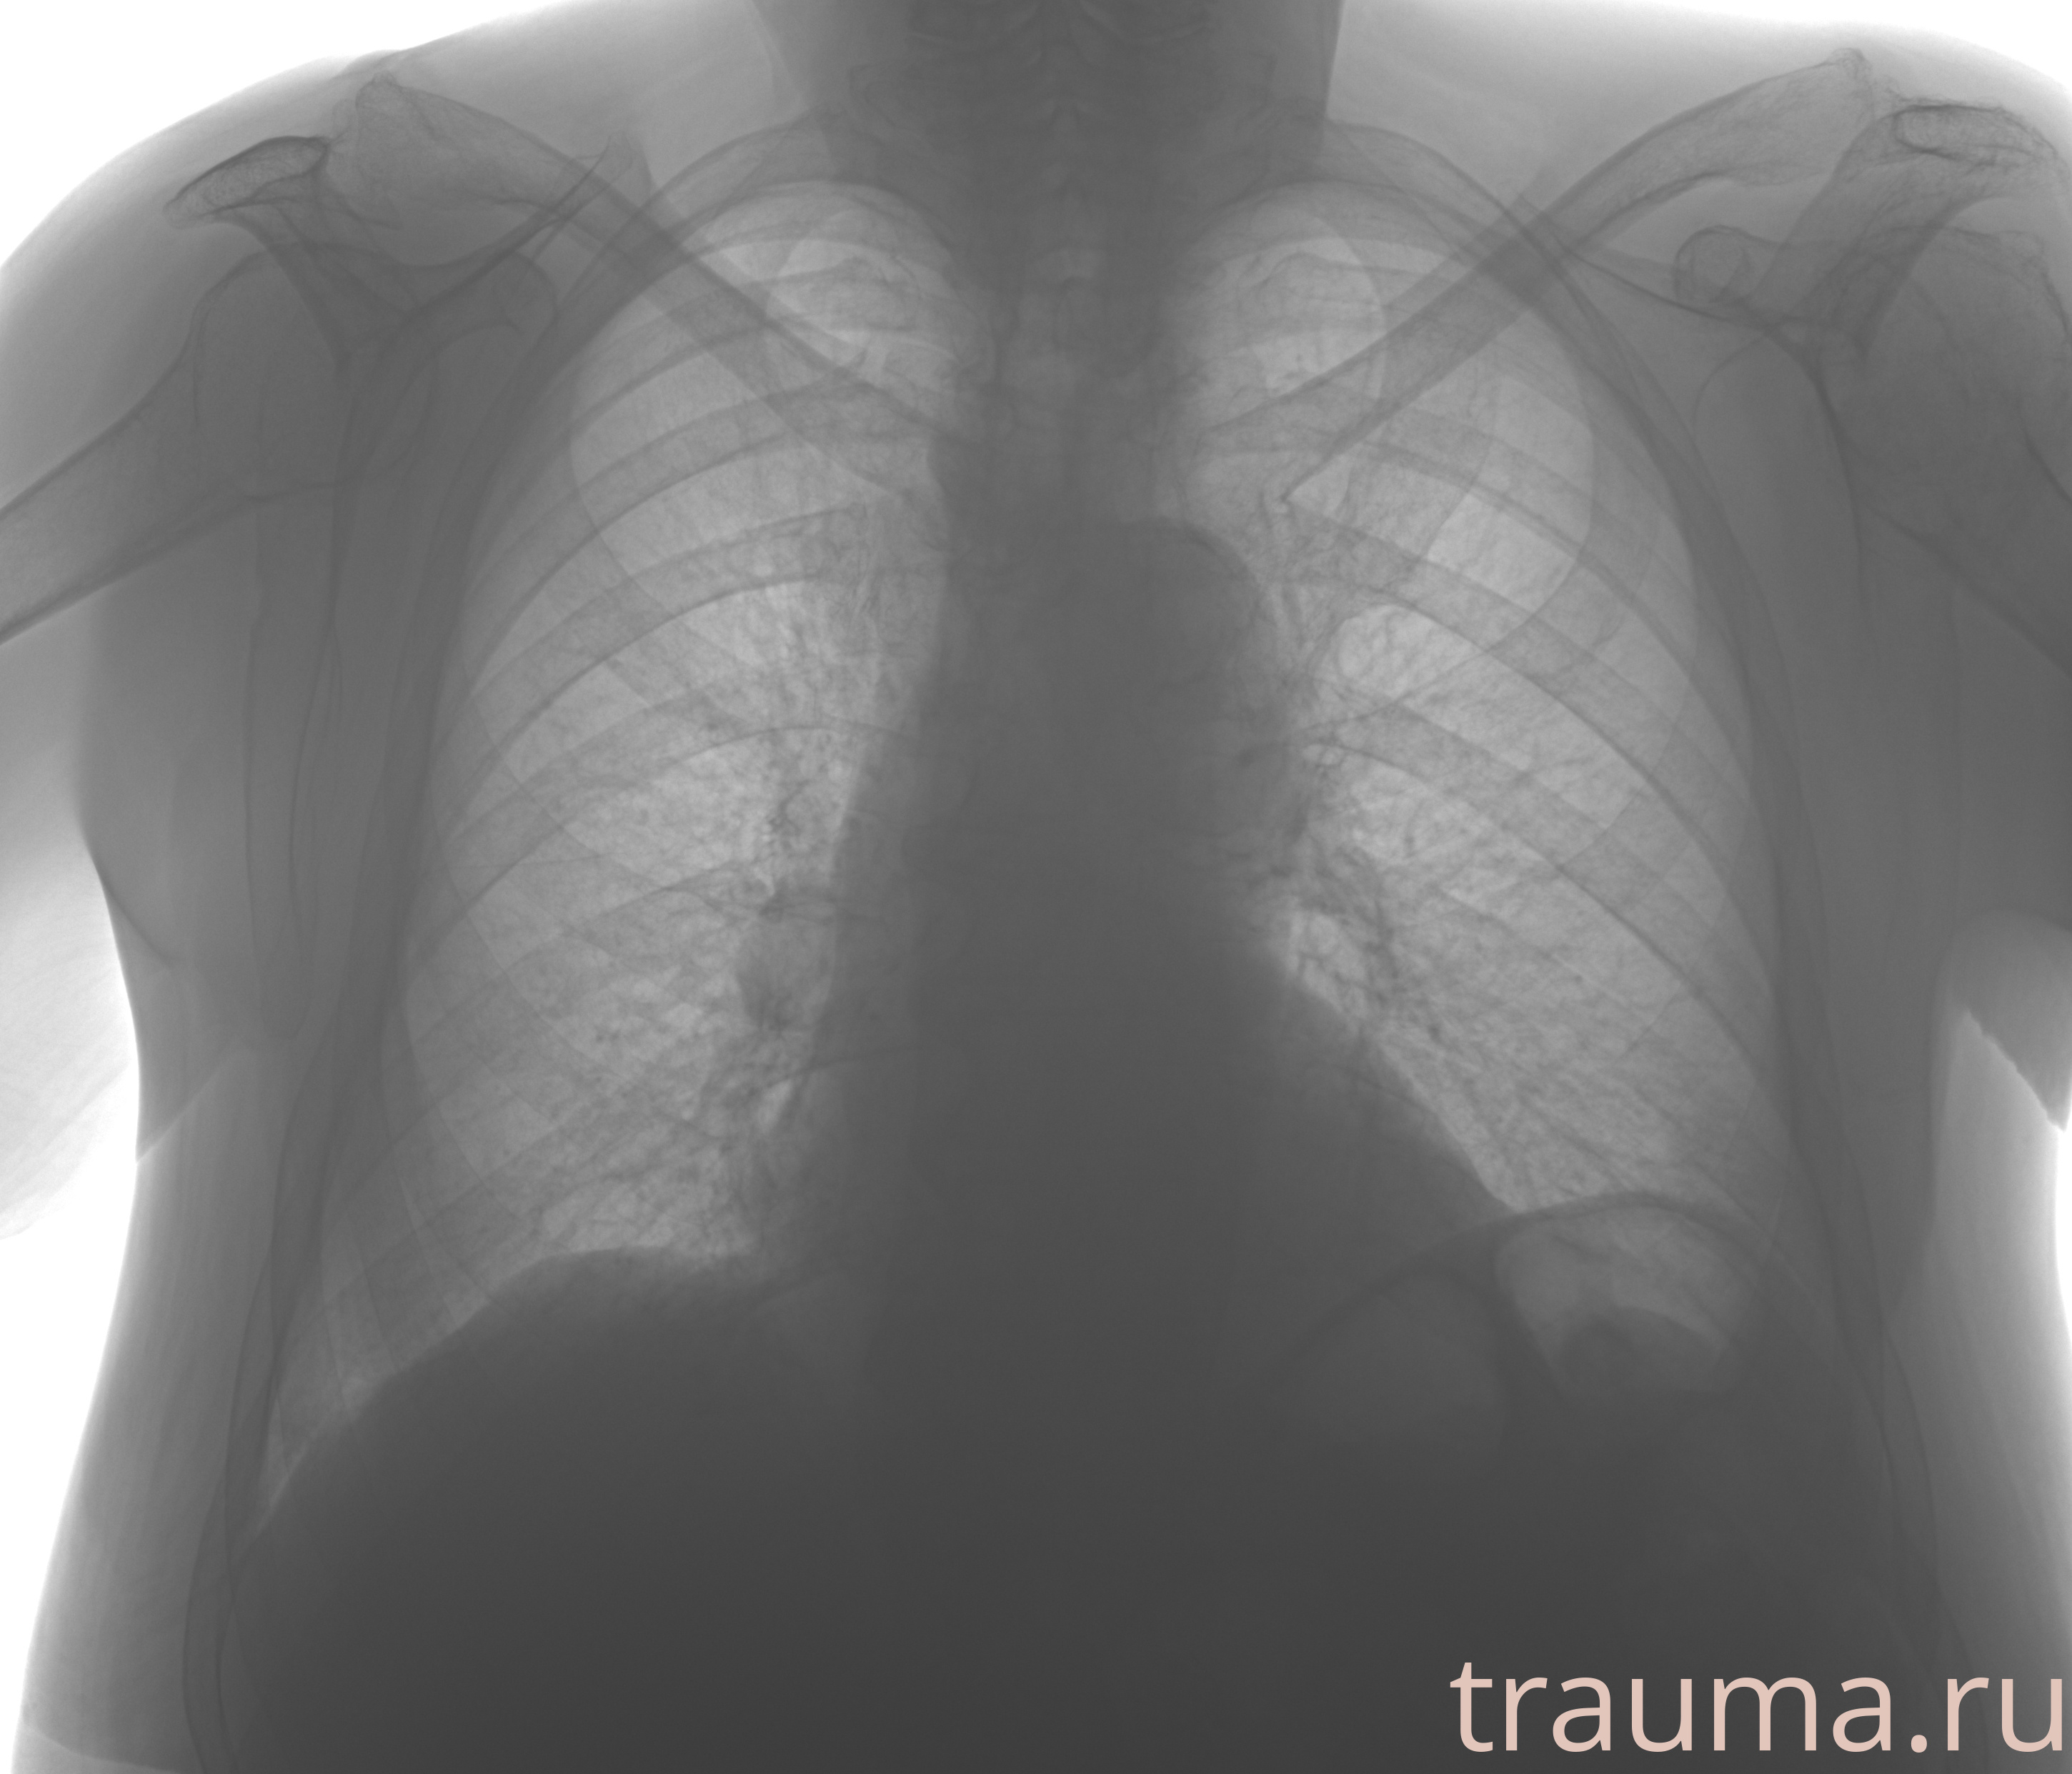

Рентгенограммы

Рентген на дому: по вашему адресу приезжает врач-рентгенолог, травматолог-ортопед с мобильным рентгеновским аппаратом, проводит диагностику травмы или заболевания, делает необходимые рентгенограммы, дает рекомендации по дальнейшему лечению. Получить качественные снимки в домашних условиях возможно благодаря уникальной методике, разработанной МосРентген Центром для института  Склифосовского

при переломе шейки бедра и пневмонии от компании МосРентген Центр - партнера Института имени Склифосовского